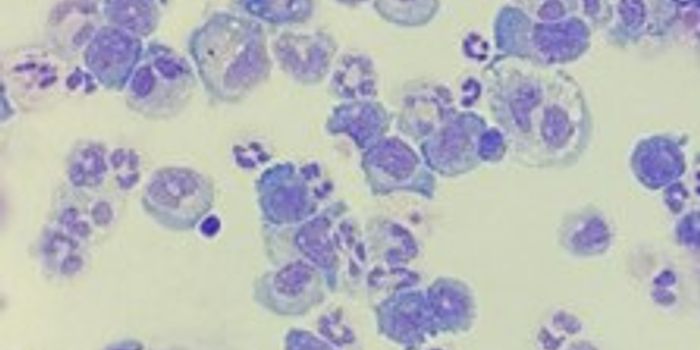

MAR 25, 2024CancerAcute myeloid leukemia (AML), a cancer that develops in the bone marrow and blood when immature white blood cells called ...

MAR 21, 2024ImmunologyAcute myeloid leukemia (AML) is a rare and aggressive hematologic malignancy. AML progresses rapidly and is indicated by ...